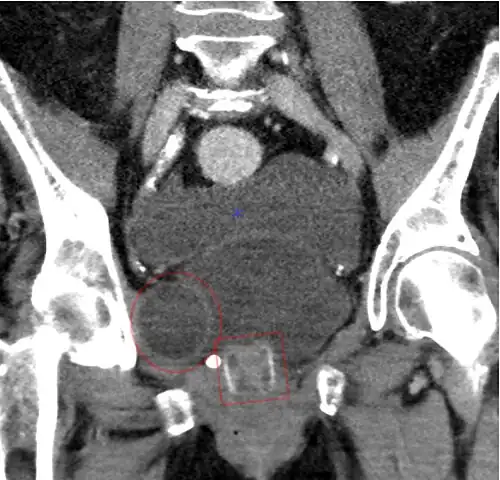

-

Tomografía computarizada (reconstrucción coronal) que muestra un AMS 800 en una mujer -